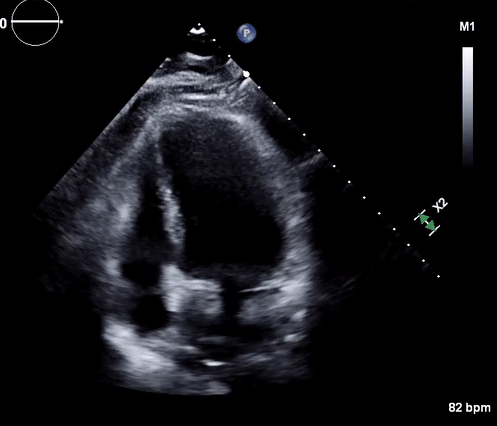

Physical, mental, and emotional stressors have been well known to adversely affect cardiac function. A rare complication of such stressors is stress cardiomyopathy, otherwise known as takotsubo cardiomyopathy. First identified in Japan in the 1990s, takotsubo cardiomyopathy classically presents with systolic dysfunction and apical ballooning. In this report, we present the case of a patient with a medical history of alcohol abuse who presented to the emergency department after being found unresponsive by her family. Transthoracic echocardiography revealed takotsubo cardiomyopathy, which was likely secondary to alcohol withdrawal. Alcohol withdrawal causes an imbalance between various neurotransmitters such as GABA and glutamate. This imbalance caused autonomic overactivity, which manifested as stress cardiomyopathy.